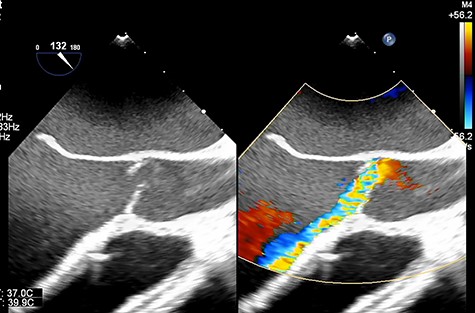

A 33-year-old man with familial dilated cardiomyopathy was urgently admitted to our hospital due to acute decompensation of heart failure with brain natriuretic peptide of 1124.5 pg/ml. Transthoracic echocardiography (TEE) showed left ventricular diastolic diameter of 75 mm, left ventricular systolic diameter of 71 mm, left ventricular ejection fraction of 20% with diffuse hypokinesis. Despite intensive medical treatment with dobutamine at 4 mcg/kg/min, his hemodynamic status did not improve: blood pressure (BP) of 91/56 (67) mm Hg, pulmonary artery pressure (PAP) of 56/18(34) mm Hg, pulmonary capillary wedge pressure of 36 mm Hg, central venous pressure (CVP) of 16 mm Hg. An Impella 5.0 catheter was emergently implanted via the right femoral artery as bridging therapy. After the initiation of Impella at the maximum flow rate, TEE showed no AI. The patient’s hemodynamic status stabilized with dopamine at 1.5 mcg/kg/min and dobutamine at 4.2 mcg/kg/min: BP of 79/66(70) mm Hg, PAP of 36/19(25) mm Hg, CVP of 9 mm Hg. Fifteen days after Impella insertion, heart transplantation was approved. HeartMate III (Abbott, Plymouth, MN, USA) implantation was performed. Intraoperative TEE detected mild AI before the Impella device was removed, which worsened to moderate AI after removal due to prolapse of noncoronary cusps (Fig. 1). At that time, BP of 107/48(67) mm Hg, PAP of 68/33(48) mm Hg and CVP of 9 mm Hg. After Park’s stitch procedure (central AV closure) was performed, diastolic arterial BP increased, with BP of 86/60(70) mm Hg, PAP of 41/25(30) mm Hg and CVP of 12 mm Hg. However, on postoperative Day 1, TEE showed the coaptation stitch on the right and noncoronary cusps had failed, causing severe AI (Fig. 2A and B). In addition, BP decreased to 84/42(49) mm Hg. Consequently, emergent AV replacement was performed. Five days after AV replacement, the patient was discharged from the intensive care unit without any complications.

(A). Transesophageal echocardiography showing severe AI at 1 day after Heart Mate III implantation. (B). Transesophageal echocardiography showing the coaptation stitch in the right and noncoronary cusps had failed at 1 day after Heart Mate III implantation.